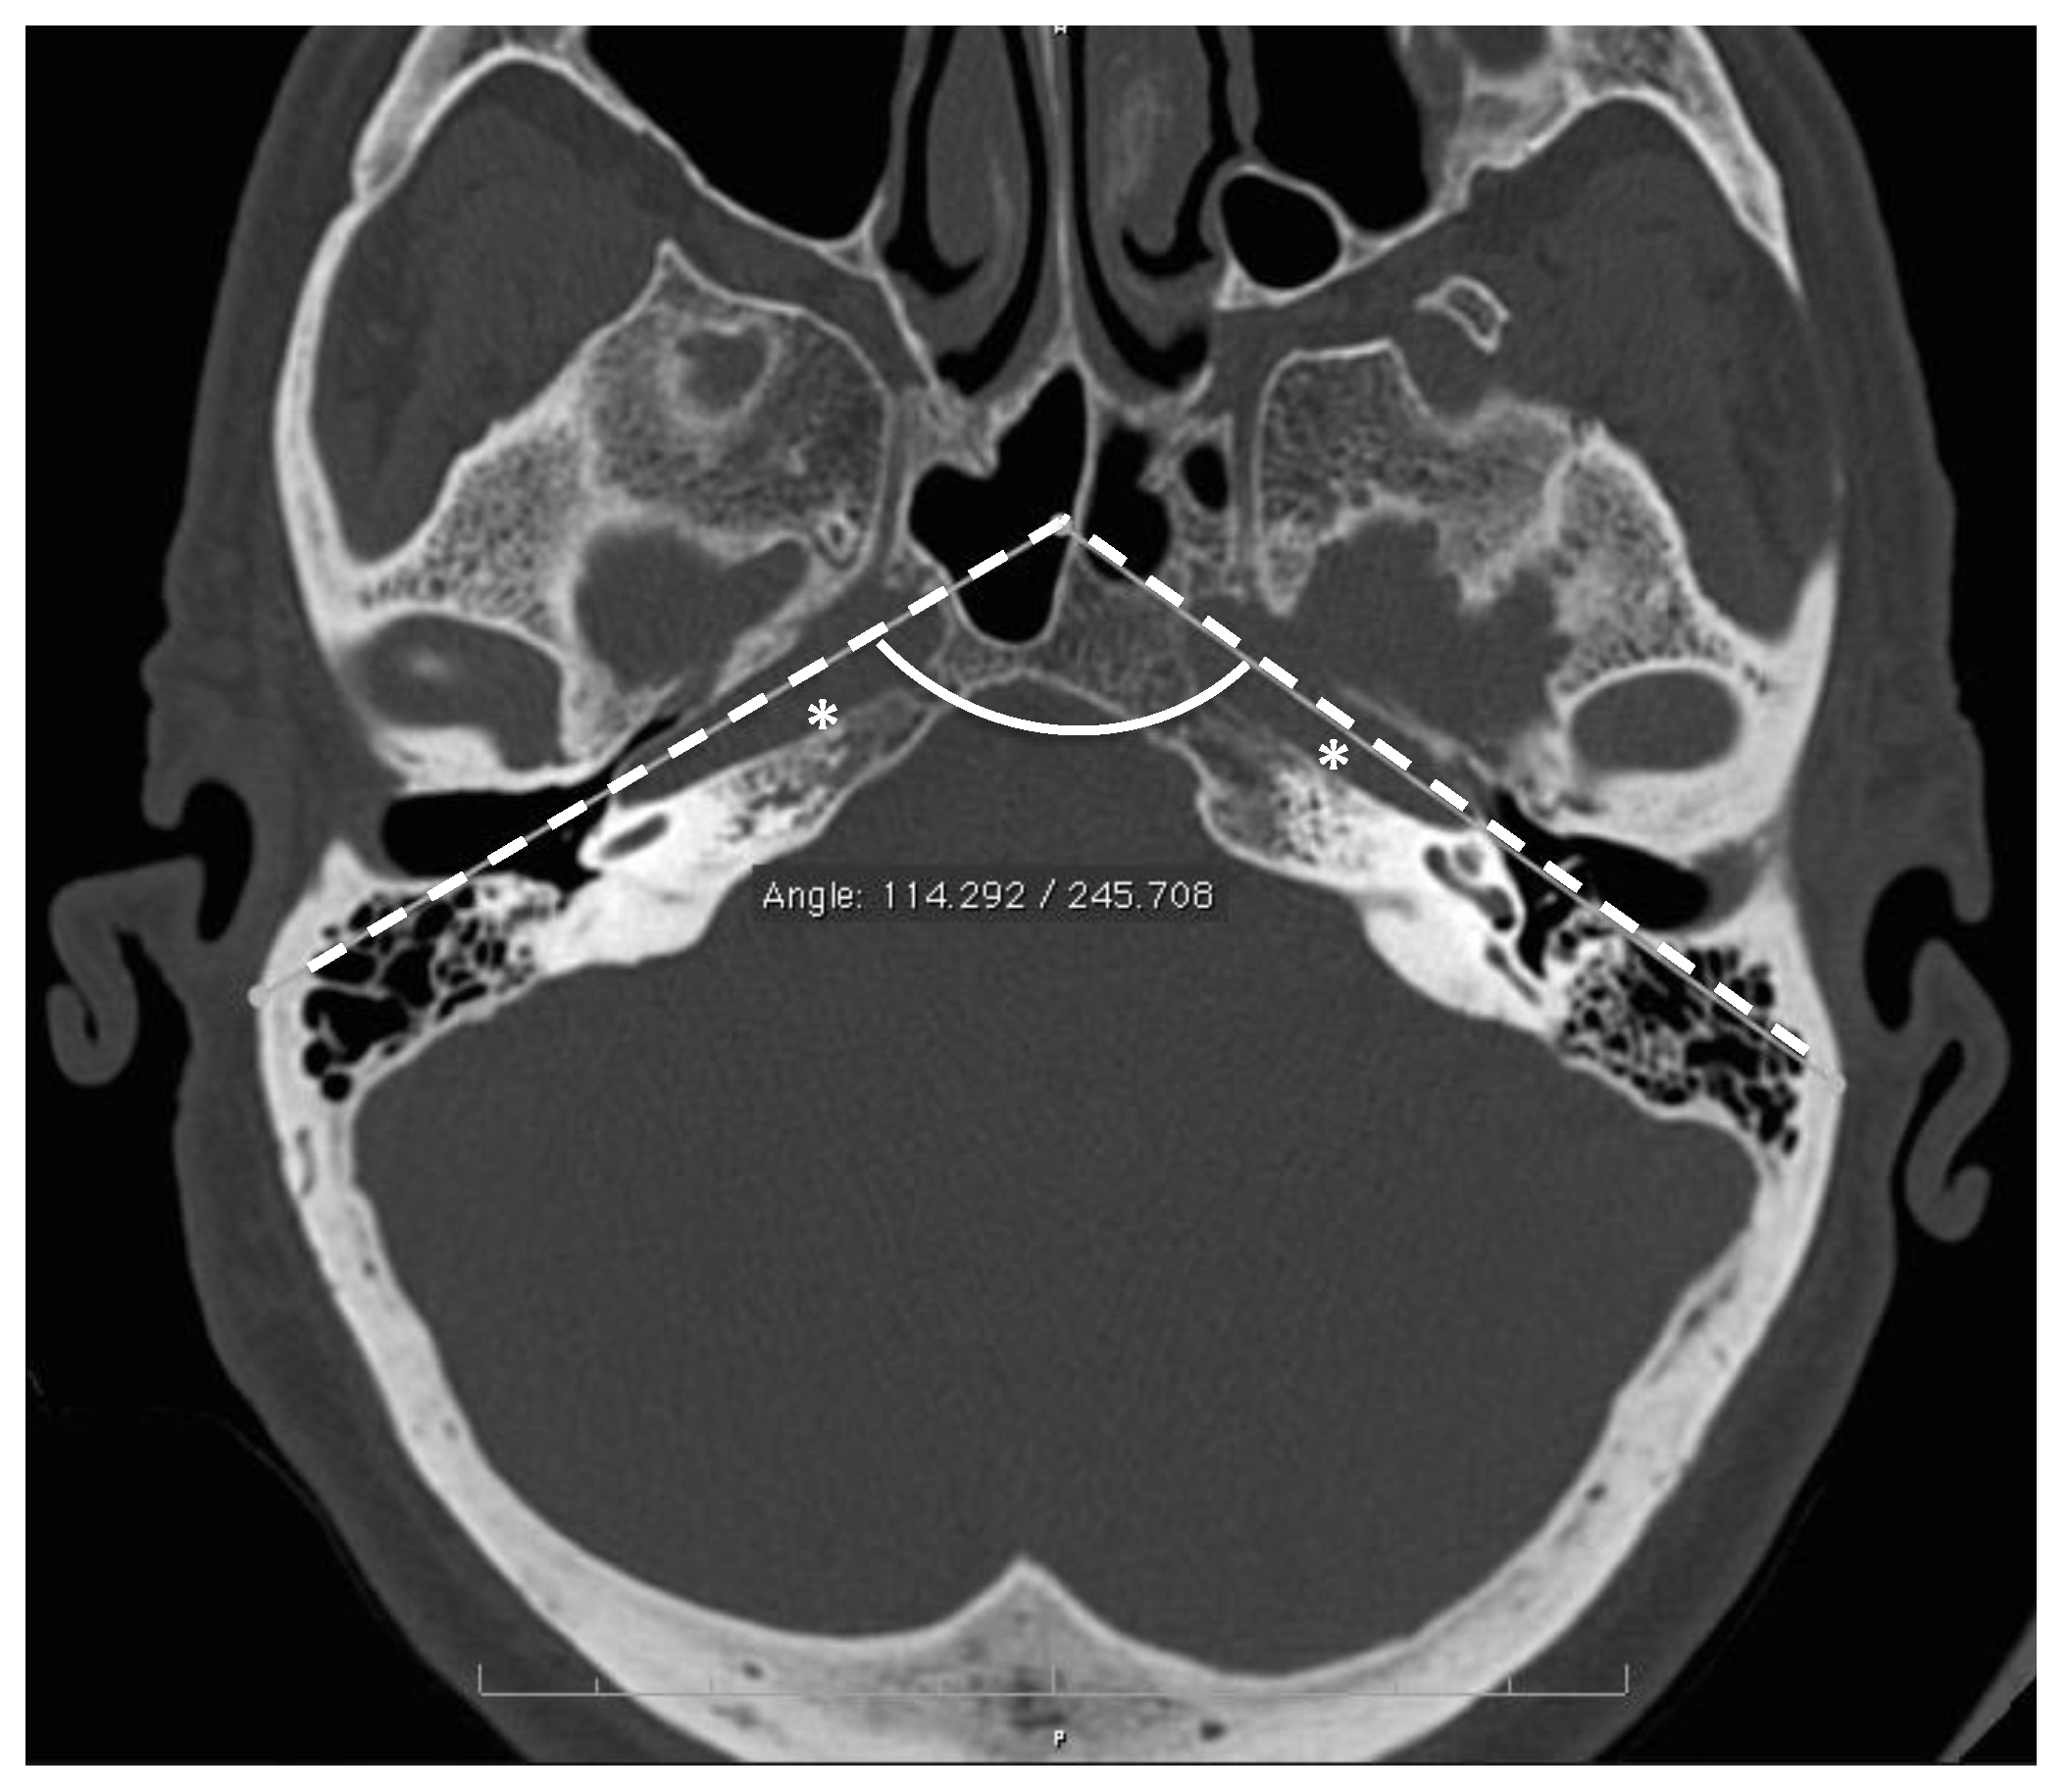

| Interpetrous angle (deg.) | 107 ± 3.7 [94–123] | - | - | 3 |